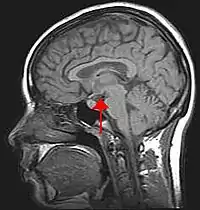

下丘脑

(英語:)又称、丘脑下部,是位于丘脑腹侧属于间脑的脑组织。下丘脑有合成和分泌各种神经激素的神经核团,参与调节机体代谢、应激反应及其他自主神经系统活动;也是调节内脏活动、内分泌功能和情绪行为等的中枢。英语 hypothalamus 源自古希腊语 ὑπό(hupó)下(under)之义,加上 θάλαμος(thálamos)腔室(chamber)之义,此因丘脑中央有第三脑室。

下丘脑被第三脑室分成左、右两半,其区域包括间脑腹侧的大部分区域,通过腦下垂體连接神经系统和内分泌系统;在人体中,它和杏核的大小相当。通常将下丘脑从前向后分为四个区:视前区、视上区、结节区和乳头体区[1][2]。视前区在视交叉前缘和前连合之间,内含视前核;视上区在视交叉上方,内含视交叉上核、视上核、室旁核及下丘脑前核;结节区则含下丘脑弓状核、腹内侧核、背内侧核;乳头体区含下丘脑后核、乳头体核。

下視丘位於腦的底部,具調節體溫、血糖、水平衡、脂肪代謝、攝食習慣、睡眠、性行為、情緒、荷爾蒙(例如:腎上腺素及皮質醇)以及自律神經系統的作用。它接收從自律神經系統而來的訊號,並決定相應的行動。當人類遇到恐懼或興奮的事情,身體的自律神經系統會向視丘下部腺體發出訊號,從而使身體加速心跳和呼吸、瞳孔擴張,並增加血液流量,以使身體能夠及時作出相應的行動。雖然它在身體佔有極為重要的地位,但它的體積只有整個腦部不足1%的空間。